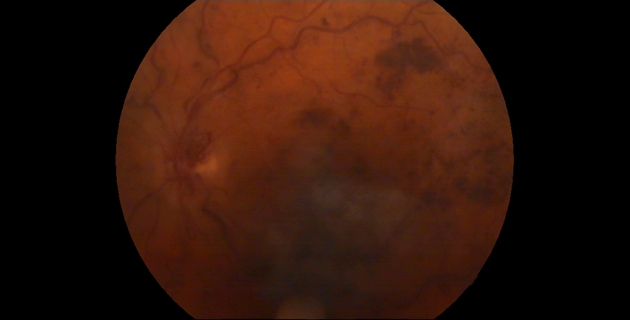

Retinaler Venenverschluss

Eine Zentralvenenthrombose oder eine Venenastthrombose ist ein Verschluss des zentralen blutableitenden Gefäßes des Auges oder eines seiner Äste. Folge ist in erster Linie eine schmerzlose Verschlechterung der Sehkraft. Bluthochdruck, Diabetes mellitus, Erkrankungen des Herz-Kreislauf-Systems und des Blutes sowie ein erhöhter Augeninnendruck sind Hauptrisikofaktoren.

Mittels Fluoreszenzangiographie und optischer Cohärenztomographie (OCT) lassen sich die einzelnen Formen darstellen und klassifizieren. Die Regulierung eines erhöhten Blutdruckes und die Behandlung von Risikofaktoren wirken sich günstig auf die Prognose aus.